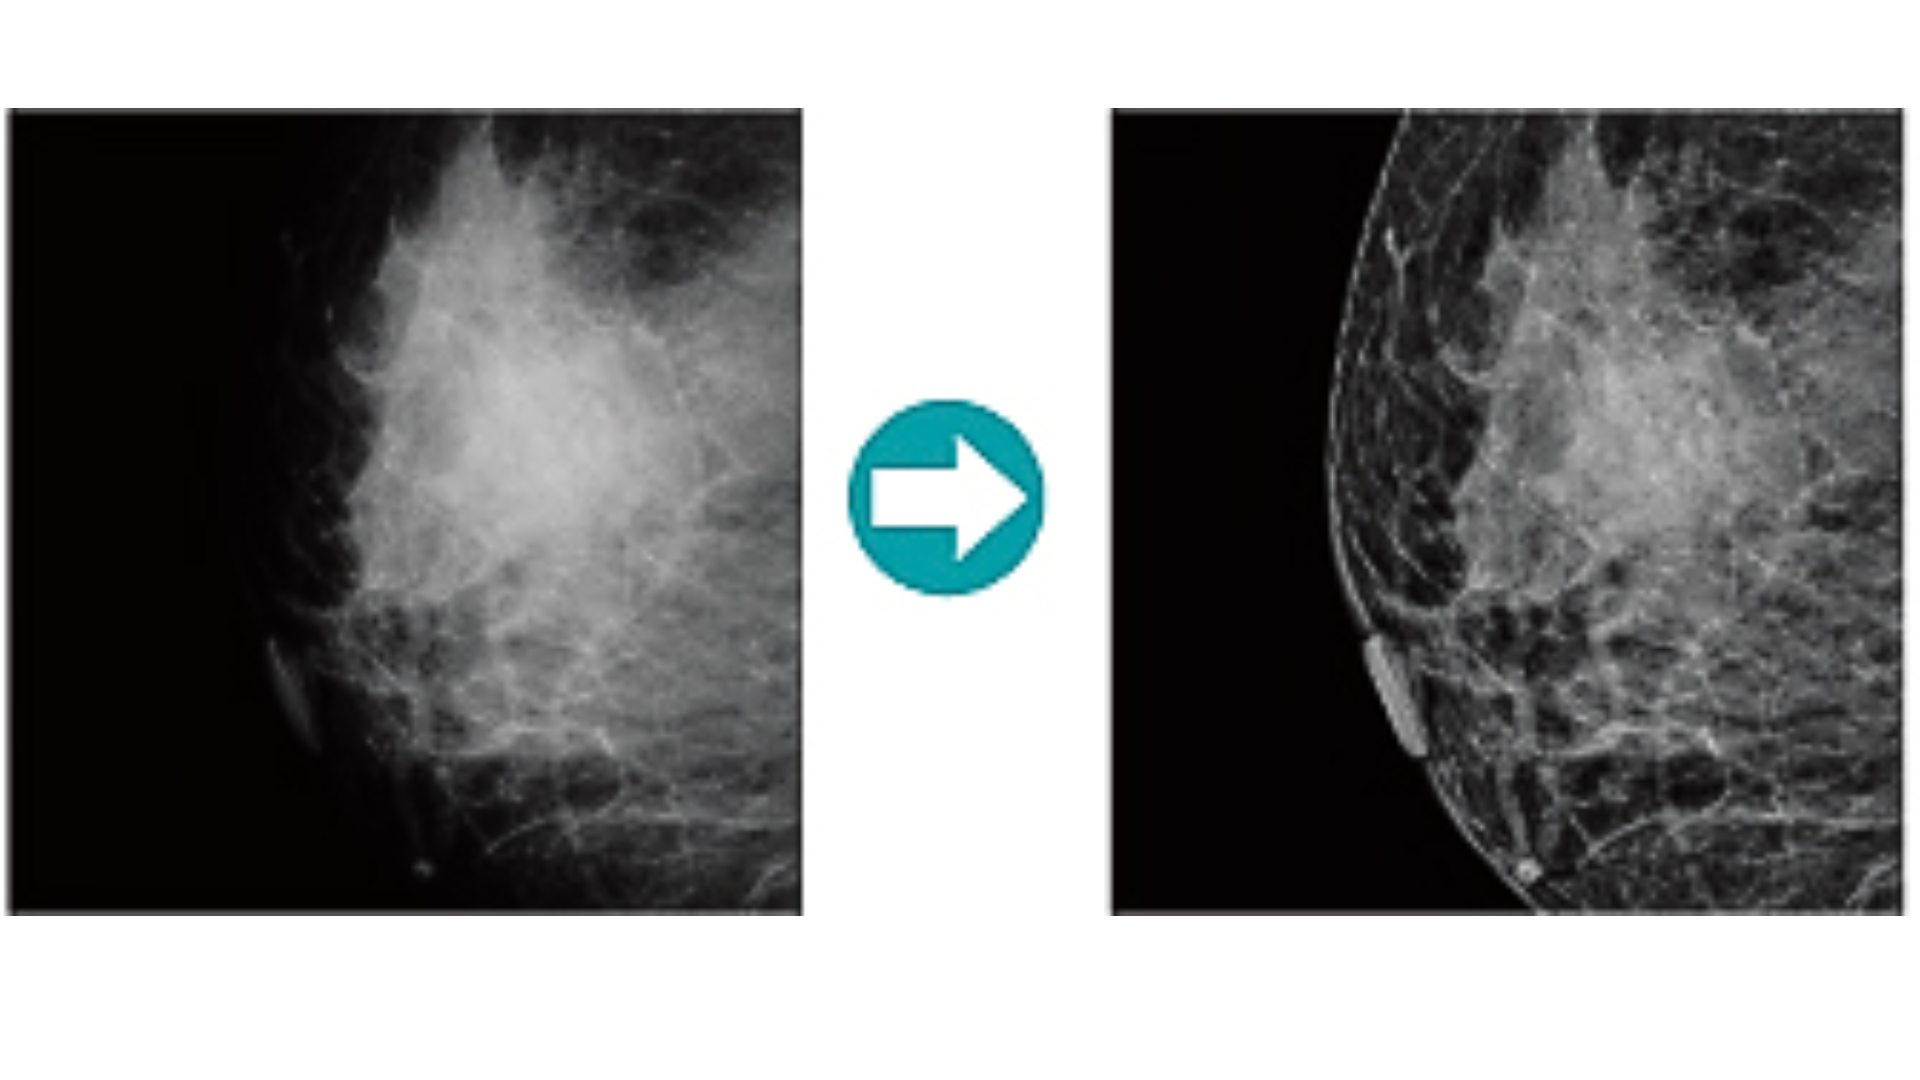

FCR PRIMA TM es un digitalizador de escritorio con una alta velocidad de procesamiento de 73 placas/hora, este modelo esta equipado con una función de lectura de imágenes de mamografía. Con una lectura de alta definición y el procedimiento más rápido y tipo compacto, este modelo aporta un flujo de trabajo sin interrupciones a su diagnóstico.